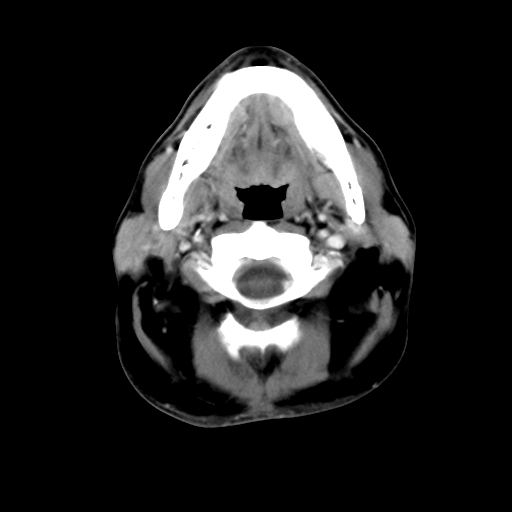

标题: CT24019:男,45岁,发现颈部肿物5个月。 [打印本页]

男,45岁,发现颈部肿物5个月,彩超示:双侧颈部及下颌部软组织增厚。

考虑双侧颈项部良性对称性脂肪增多症。